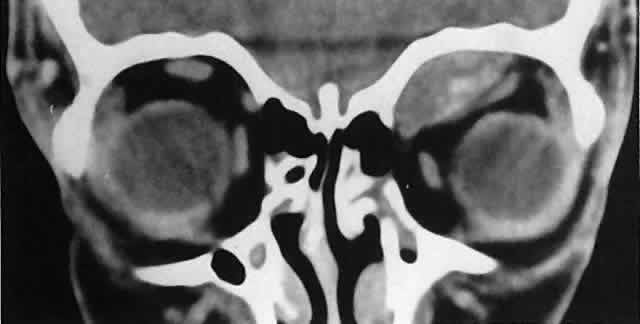

RHABDOMYOSARCOMA Rhabdomyosarcoma is the most common soft-tissue sarcoma in patients younger than 15 years of age and the most common primary orbital malignancy in childhood. These facts should not imply its frequent occurrence. Including all body sites, the annual incidence of childhood rhabdomyosarcoma in the United States is approximately 225 cases.2 The orbit is the site of origin in 5% to 25% of cases.3,4 However, site distribution varies with age. In children 5 to 9 years of age, for example, approximately 40% of primary rhabdomyosarcomas involve the orbit or eyelid.2 Although relatively rare, the tumor has a devastating natural history and demands a high index of suspicion in all cases of pediatric proptosis. Orbital rhabdomyosarcomas are slightly more common in females, with a 0.79 to 1 male-to-female ratio.2 The average age of presentation is 7.8 years, but the tumor may be present at birth and has been reported in patients as old as 78 years.5 A positive family history and associated anomalies have at times been identified, but these are exceptions rather than the rule. Classically, orbital rhabdomyosarcoma presents in an abrupt manner, with rapid progression of proptosis over days to weeks. A somewhat more indolent course does not exclude the diagnosis, however. Vigilance also should be exercised when rapidly expanding eyelid lesions are encountered. Rhabdomyosarcoma may present as ptosis or an eyelid mass rather than with proptosis.4 An eyelid rhabdomyosarcoma can occur as a congenital lesion.6 Within the orbit, rhabdomyosarcoma occurs most often, but not exclusively, in the superior nasal quadrant, with downward and outward displacement of the globe. CT scans show the topography of the orbital mass (Fig. 1A), as well as the possible extension into adjacent bone, paranasal sinuses, or the intracranial cavity. The circumscription that may be noted on CT is relative, because the lesion is not encapsulated and microscopically infiltrates normal tissue. Echography shows internal echoes of low-to-medium amplitude. Because the cellular tumor absorbs acoustic energy, the amplitude of the spikes falls off somewhat through the lesion (see Fig. 1B and C). MRI can help define the tumor's relationship to extraocular muscles (Fig. 2). The clinical diagnosis must be confirmed by biopsy. Because of the risk of seeding the biopsy tract, a transcranial approach should be avoided. If possible, the periosteum should not be violated because it presents a relative barrier to tumor invasion. Depending on its location, the lesion should be approached transconjunctivally or with an eyelid crease incision/transseptal dissection. The surgeon must balance the benefit of complete gross tumor resection with the risks of functional impairment and tumor dissemination that may accompany that effort. Tissue samples should be fixed in formaldehyde solution and glutaraldehyde for light and electron microscopic study. In addition, the value of immunohistochemical differentiation has been established for some time, and the potential uses of molecular genetic studies are rapidly emerging. Consequently, the procurement of fresh or frozen tissue, or both, has been given the highest priority by the Biopathology Discipline within the Intergroup Rhabdomyosarcoma Study Group (IRSG).2 These techniques can facilitate the diagnosis of poorly differentiated tumors, and they may refine diagnostic and prognostic classifications, identify candidate genes, and contribute to potential gene therapies. Since the inception of IRSG-I in 1972, the multicenter collaboration has enrolled the overwhelming majority of patients diagnosed with rhabdomyosarcoma in the United States and has contributed significantly to enhanced patient survival. Patients with orbital tumors had a 96% versus 83% failure-free survival in IRSG-IV compared with those in the IRSG-III.2 As of the year 2000, with the IRSG-V study underway, the overall (all primary sites) 5-year survival of children and adolescents with nonmetastatic and metastatic tumors was approaching 80%. This progress reflects advances in diagnostic imaging and multimodal treatment, including chemotherapy (e.g., agents, combinations, timing), radiation therapy (e.g., doses, fractionation, timing), and surgery (e.g., diagnostic biopsy, local staging, salvage procedures). Therapeutic protocols have evolved over the past 30 years, but they also have not been uniform at any given point in time. Rather, they have been tailored to the patient's level of risk, as determined by multiple prognostic factors (Table 3). The concept of “risk-appropriate therapy”7 recognizes, for example, that a 6-year-old child with an embryonal rhabdomyosarcoma confined to the orbit might do well with a relatively simple chemotherapy protocol, avoiding the late adverse effects of high-dose radiation. Conversely, an 18-year-old patient with an alveolar rhabdomyosarcoma arising in the retroperitoneum, with metastases at presentation, needs aggressive, complex chemotherapy and radiation, and may still do poorly. Prognostic factors considered by the multidisciplinary team include the presence of gross or microscopic residual tumor, and this determination currently is being redefined with molecular techniques that may show residual disease even without microscopic evidence2; whether tumor is confined to the anatomic site of origin or invades surrounding tissues; tumor size, with 5 cm considered a breakpoint; regional lymph node involvement; and distant metastasis. Body site plays a role, and the orbit is relatively favored. The age of the patient at diagnosis is a strong independent predictor of outcome.7 The current pathologic classification for childhood rhabdomyosarcomas by prognosis2 is as follows: